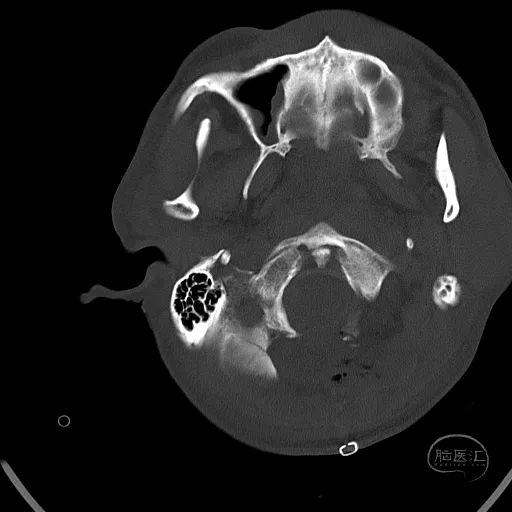

骨窗显示枕骨粉碎性骨折,累及枕骨大孔左侧,齿突尚居中。